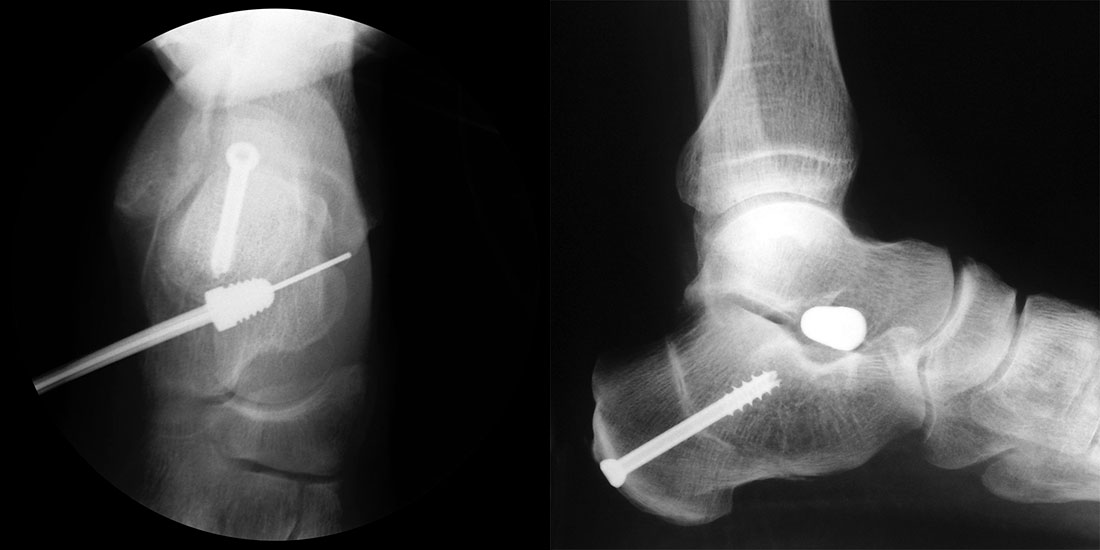

Bei Rückfussfehlstellungen ist meist eine knöcherne Korrektur des Kalkaneus indiziert. Dabei wird das Fersenbein im Bereich des Tuber calcanei durchtrennt und der Achillessehnenansatz nach medial oder lateral geschoben. Zusätzlich ist eine Rotation des Tuber möglich, wodurch sich der Korrektureffekt noch verstärkt. Durch die Wahl der Osteotomieebene kann die Verscheibung mit einer Verlängerung oder Verkürzung des Fersenbeins kombiniert werden. Die Osteosynthese erfolgt typischerweise durch perkutan eingebrachte Schrauben.

Kanülierte Schrauben bis 80 mm Länge.

Kirschnerdraht mit 2,0 mm zur Verschiebung des Tuber calcanei.